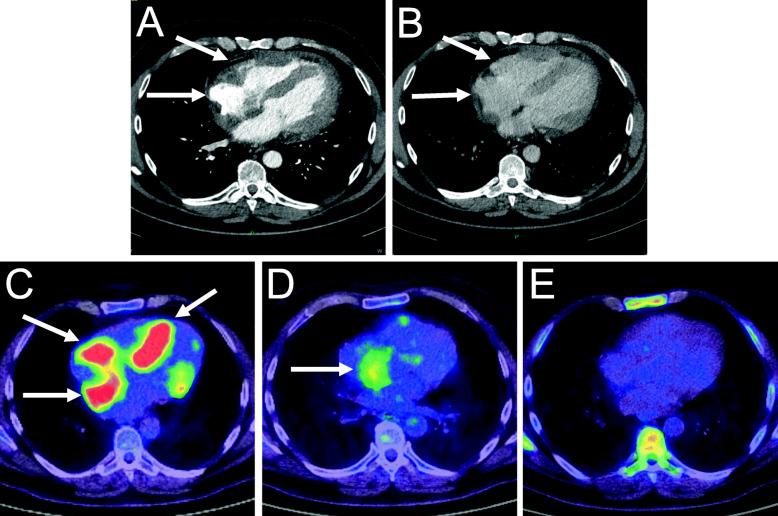

Forty-eight-year-old diffuse large B cell lymphoma patient was admitted to our emergency department with chest pain, effort dyspnea, and fever. The patient had normal blood pressure, blood oxygen saturation, sinus tachycardia, fever, crackles over the left lower lobe, novum incomplete right bundle branch block with Q waves and minor ST alterations, elevated C-reactive protein, high-sensitivity troponin-T, and d-dimer levels. Chest X-ray revealed consolidation on the left side and enlarged heart. Bed side transthoracic echocardiography showed inferior akinesis with pericardial fluid. Coronary angiography showed no occlusion or significant stenosis. Chest computed tomography demonstrated the progression of his lymphoma in the myocardium. He was admitted to the Department of Hematology for immediate chemotherapy and he reached complete metabolic remission, followed by allogeneic hematopoietic stem cell transplantation. Unfortunately, about 9 months later, he developed bone marrow deficiency consequently severe sepsis, septic shock, and multiple organ failure what he did not survive.

Our case demonstrates a very rare manifestation of a heart metastasis. ACS is an unusual symptom of cardiac tumors. But our patient's intramyocardial lymphoma in the right atrium and ventricle externally compressed the right coronary artery and damaged the heart tissue, causing the patient's symptoms which imitated ACS. Fortunately, the quick diagnostics and immediate aggressive chemotherapy provided the patient's remission and suitability to further treatment.

一名48岁的弥漫性大B细胞淋巴瘤患者因胸痛、劳力性呼吸困难和发热入住我院急诊科。患者血压正常、血氧饱和度正常、窦性心动过速、发热、左下叶可闻及湿啰音、新出现的不完全性右束支传导阻滞伴Q波和轻微ST段改变、C反应蛋白升高、高敏肌钙蛋白T及D - 二聚体水平升高。胸部X线显示左侧实变及心脏增大。床旁经胸超声心动图显示下壁运动减弱伴心包积液。冠状动脉造影显示无闭塞或明显狭窄。胸部计算机断层扫描显示其淋巴瘤在心肌内进展。他被收入血液科立即进行化疗,并达到完全代谢缓解,随后接受异基因造血干细胞移植。不幸的是,约9个月后,他出现骨髓抑制,继而发生严重脓毒症、感染性休克和多器官功能衰竭,最终死亡。

我们的病例展示了一种非常罕见的心脏转移表现。ACS是心脏肿瘤的一种不寻常症状。但我们患者右心房和心室的心肌内淋巴瘤向外压迫右冠状动脉并损伤心脏组织,导致患者出现类似ACS的症状。幸运的是,快速诊断和立即积极化疗使患者缓解并适合进一步治疗。